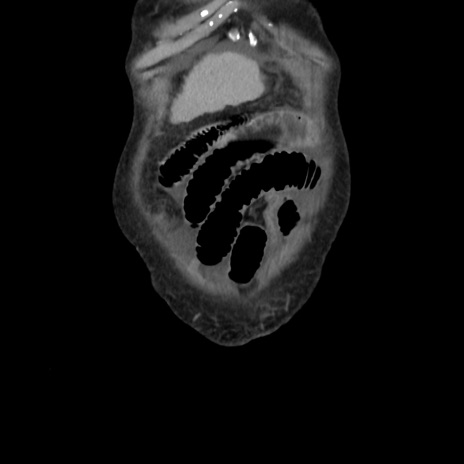

横断像